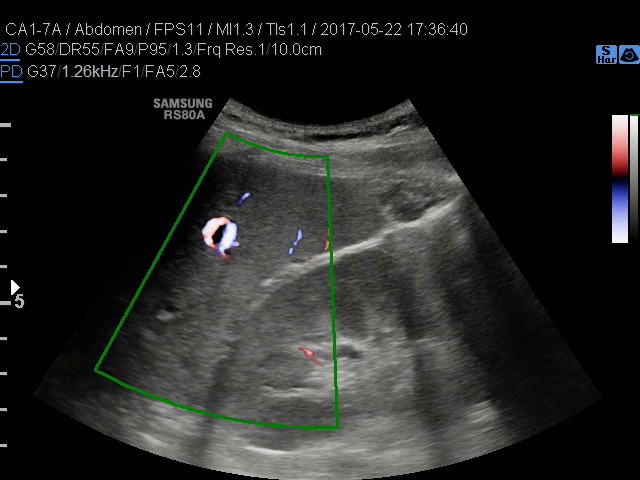

• USG jamy brzusznej

z oceną wątroby, trzustki, nerek, śledziony, pęcherza, gruczołu krokowego, dużych naczyń jamy brzusznej oraz przestrzeni okołoaortalnej.

• USG doppler naczyń

kończyn górnych i dolnych - żylnych lub tętniczych

• USG jamy brzusznej z oceną wątroby, trzustki, nerek, śledziony, pęcherza, gruczołu krokowego, dużych naczyń jamy brzusznej oraz przestrzeni okołoaortalnej

• USG doppler aorty i naczyń biodrowych

• USG doppler układu wrotnego

Rozszerzamy ofertę naszych pracowni: